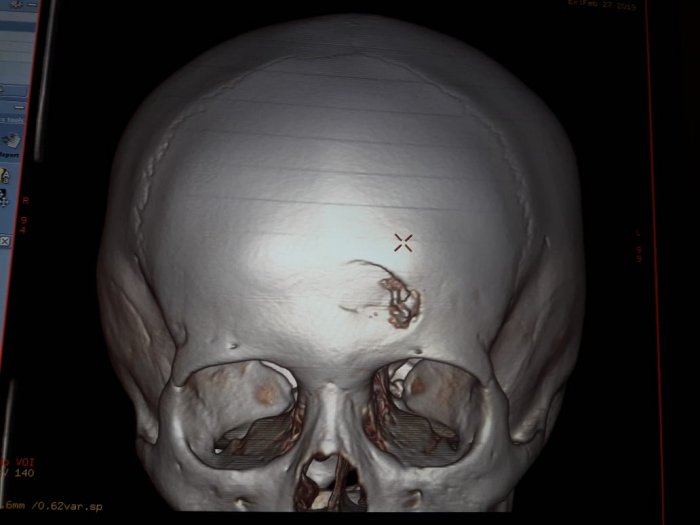

В Жанаозене ребенок упал с высоты четырех метров и выжил

Благодаря усилиям врачей, упавшего семилетнего мальчика спасли. Сейчас состояние ребенка стабильно тяжелое. Об этом сообщили в управлении здравоохранения Мангистауской области.

Фото предоставлено управлением здравоохранения Мангистауской области.

Инцидент произошел в ночь с 27 на 28 февраля в Жанаозене. По словам родителей, их сын, играя на стройке, упал с высоты четырех метров и ударился об камень.

- Пациент - мальчик 2012 года, с диагнозом тяжелая открытая черепно-мозговая травма, вдавленный перелом лобной кости, кортикальный ушиб левой лобной доли. Ушибленная рана лобной области. Из областной детской больницы в Жанаозен в экстренном порядке выехал детский нейрохирург Ербол Кенжевалов. Произведена первичная хирургическая обработка раны, наложены швы, - сообщили в управлении здравоохранения Мангистауской области.

По словам врача, могут быть вторичные осложнения, такие, как нагноения послеоперационной раны, менингит или вентрикулит - из-за сильного загрязнения раны, от песка и грязи.